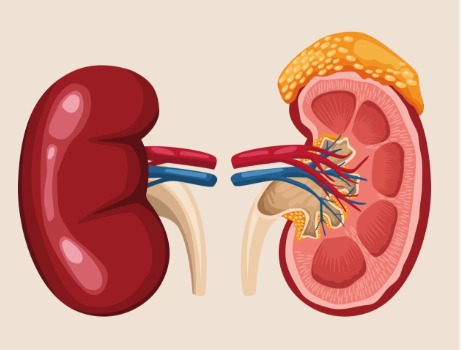

Liver & Kidney Care

Holistic management of Liver & Kidney diseases. We focus on improving organ function and preventing further complications.

Liver & Kidney Disease

लिवर एवं गुर्दे संबंधित बीमारियां

Renal/kidany

गुर्दे की पथरी